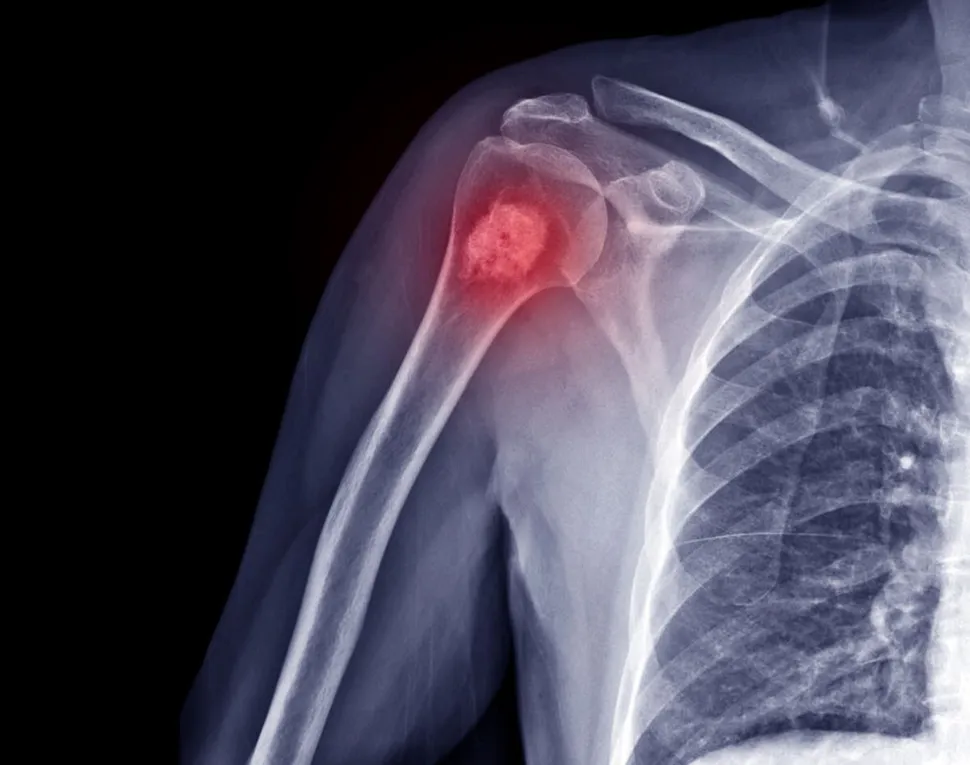

2.06 — What are lytic and focal bone lesions and how common are they?

The difference between a lytic and focal bone lesion is useful to know, especially if you have bone lesions at diagnosis.